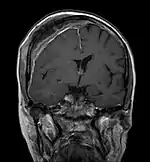

Imagerie par résonance magnétique

Avec l'IRM, on peut en particulier obtenir de bonnes images des tissus mous. C'est un processus idéal pour le diagnostic des métastases spinales (métastases des vertèbres). Avec l'IRM, on peut en outre rendre visible des complications supplémentaires dans la région des métastases spinales, comme des infections ou des blessures des tendons et ligaments, des œdèmes de la moelle osseuse après une fracture récente[120],[121], ou la compression de structures nerveuses[18]p. 16. Au moyen de séquences STIR, il est possible d'évaluer l'âge d'une fracture. Pour la détection des métastases, la pondération T1 avec des produits de contraste au gadolinium, comme l'acide gadotérique est particulièrement bien adaptée. Le produit de contraste s'accumule particulièrement fort dans les métastases[18],[122].

Pour le diagnostic des récidives (2), l'IRM est plus adapté que le scanner. Par exemple, les implants de titane font moins d'artefacts pour l’IRM[87],[123].

IRM natif avec pondération T1.

IRM sagittal natif avec pondération T1. On voit clairement l’extension jusqu'aux lames vertébrales.